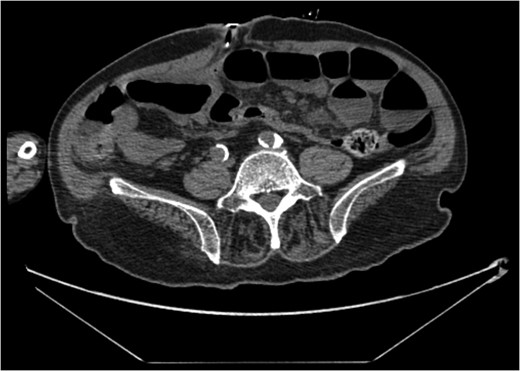

A 68-year-old male nursing home resident presented following dislodgement of a percutaneous endoscopic colostomy (PEC) tube originally sited to prevent recurrent sigmoid volvulus. Computed tomography demonstrated tube migration into the lumen of the recto-sigmoid junction, where it remained for 12 days before passing spontaneously. During this period, the patient remained asymptomatic; the residual colocutaneous fistula functioned as a decompressive valve. Originally, the patient was due to be discharged with early flexible sigmoidoscopy follow-up. However, complex social issues delayed discharge. During his admission, a second PEC tube was successfully inserted next to the previous colostomy site without complication. This is an unusual case and no similar episodes of asymptomatic PEC migration have been reported. We demonstrate that such cases may be offered an appropriate trial of conservative management. Here, we describe our experience and critically appraise the literature.

The patient remained asymptomatic with a soft, non-tender abdomen. The only abnormal clinical finding was the absence of a PEC tube from a patent periumbilical colostomy site.

The patient remained well and the PEC tube passed spontaneously on Day 12, during a bowel motion.

Tube migration leading to perforation and frank peritonitis has been described elsewhere [10]. However, there are no cases of asymptomatic dislodged PEC tubes. Following discussion with gastroenterology and colorectal surgery, the decision was made to let the PEC pass spontaneously or remove it during early follow-up flexible sigmoidoscopy. The PEC tube was naturally expelled on Day 12 without complication.